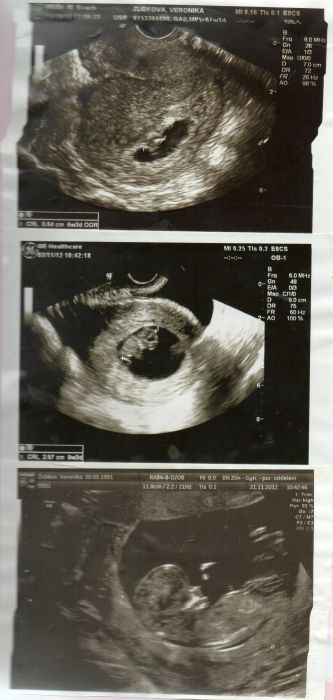

Holky teď se koukám na fotky jak byl malý mimčo a mám tu ultrazvuky mrkněte první fotka je 6+3 druhá 9+3 a ta poslední je právě z toho velkého vyšetření nějak kokem 12tt já byla ve Zlíně v nemocnici a nikdo se mě neptal jestli chci nebo ne prostě mě tam objednali.. já myslela, že se to musí, ale není to nic hrozného jen ultrazvuk a krev a dokonce mi tam i řekli, že to vypadá na kluka, že to šlo hezky vidět.... a trefili se :-)